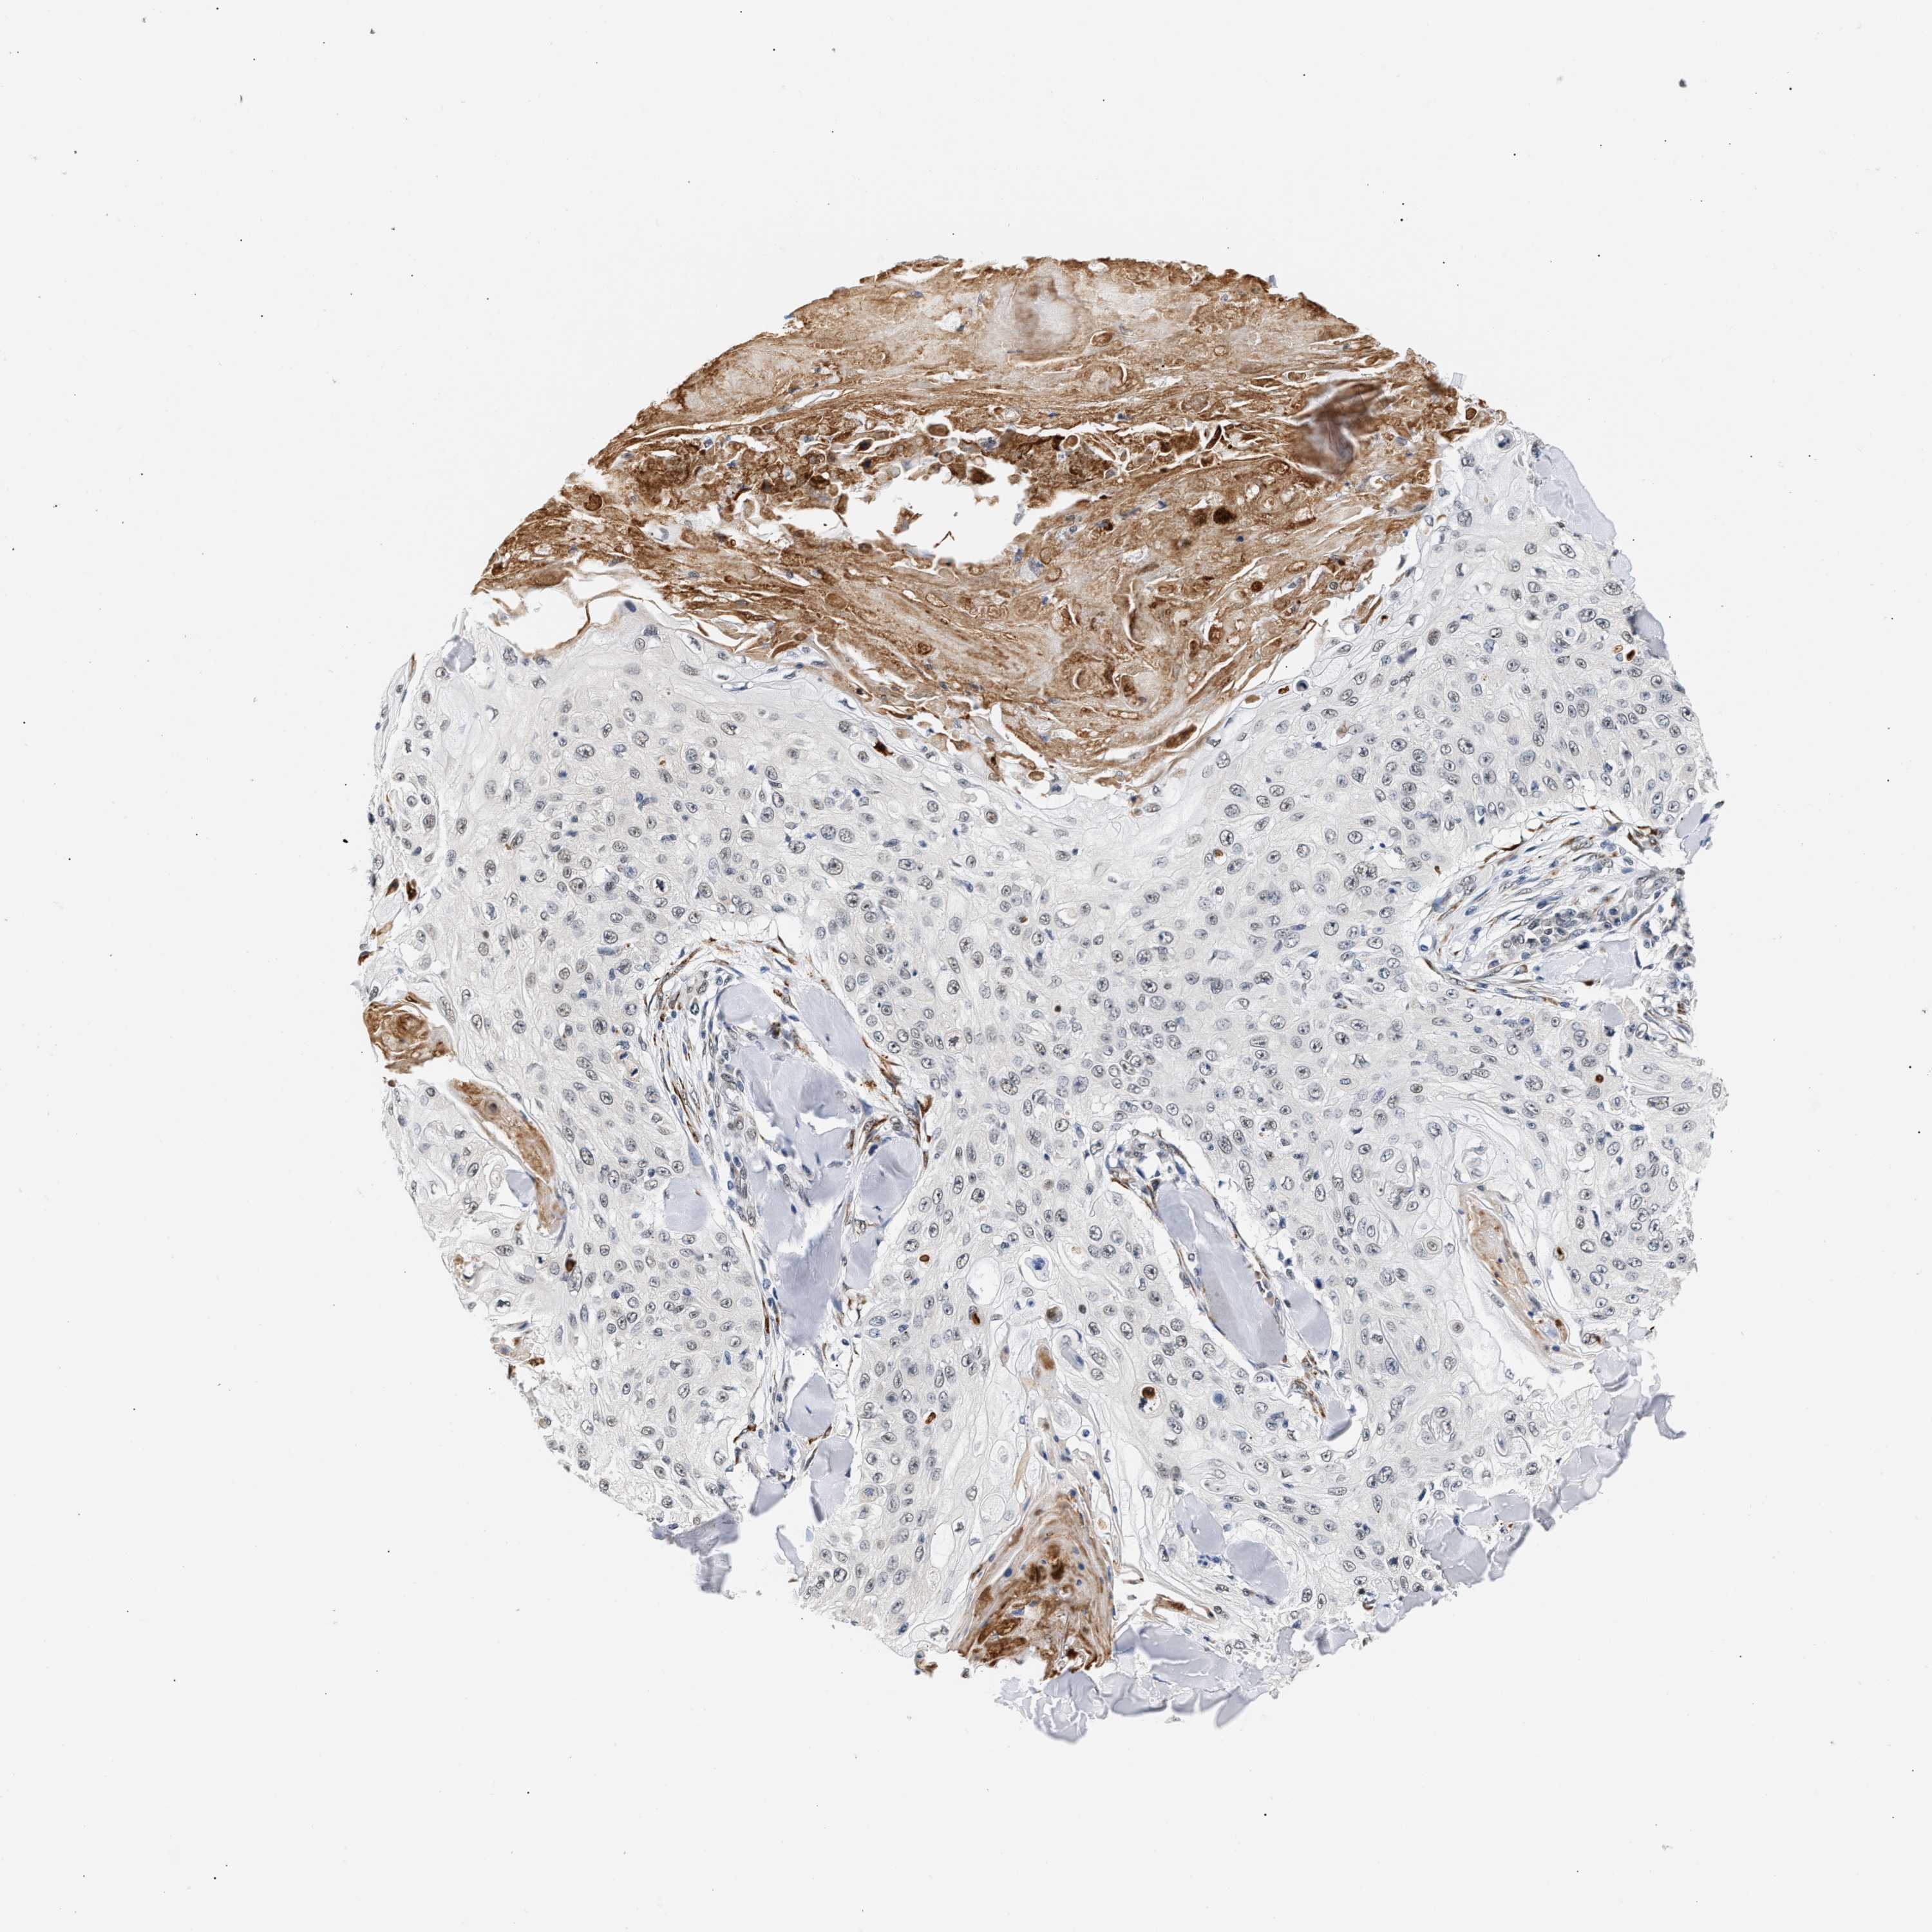

SKIN CANCER - Protein expressioni

A mouse-over function shows sample information and annotation data. Click on an image to view it in a full screen mode. Samples can be filtered based on level of antibody staining by selecting one or several of the following categories: high, medium, low and not detected. The assay and annotation is described here.

Antibody stainingi

Antibody staining in the annotated cell types in the current human tissue is reported as not detected, low, medium, or high, based on conventional immunohistochemistry profiling in selected tissues. This score is based on the combination of the staining intensity and fraction of stained cells.

Each image is clickable and will lead to virtual microscopy that enables deeper exploration of all samples and also displays staining intensity scores, fraction scores and subcellular localization as well as patient and tissue information for each sample.

Antibody HPA019096

Antibody HPA019687

Basal cell carcinoma

Squamous cell carcinoma, NOS

Squamous cell carcinoma, metastatic, NOS